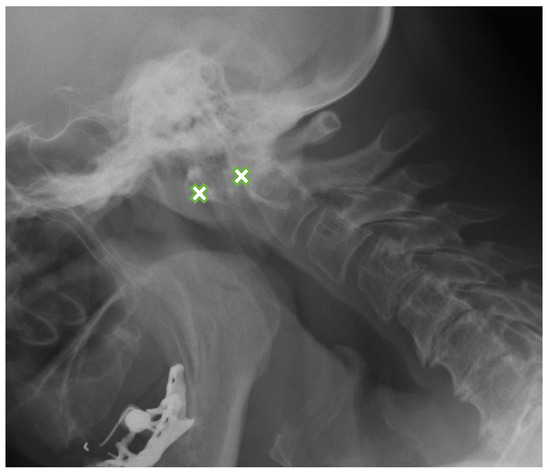

Out of 240 patients in the RA group, 179 (75%) had RA-related abnormalities of the cervical spine seen on radiographs and/or MRI. The most common lesions were anterior AAS (Figure 1) diagnosed in 140 patients (58%) with radiographs and in 78 (33%) with MRI, SAS seen in 139 patients (58%) on radiographs and in 102 patients (43%) with MRI, and demineralization diagnosed in 114 patients (48%) entirely with radiographs (Table 1).

Figure 1.

Lateral flexion view radiograph in a 63-year-old female with rheumatoid arthritis shows anterior AAS-8.8 mm (between crosses). AAS: atlanto-axial subluxation.